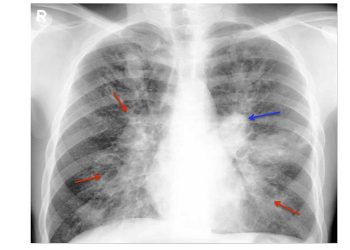

CT scans are often used to confirm the diagnosis and give a detailed view of the fracture pattern. They can identify displaced fractures, joint involvement, or bone fragments. CT scans also help in pre-surgical planning, especially in unstable or multi-fragment injuries.

Ultrasound or FAST scans may be done in trauma cases to check for internal bleeding in the abdomen or pelvic cavity. MRI may be used to assess soft tissue damage, ligaments, or spinal involvement if neurological symptoms are present.